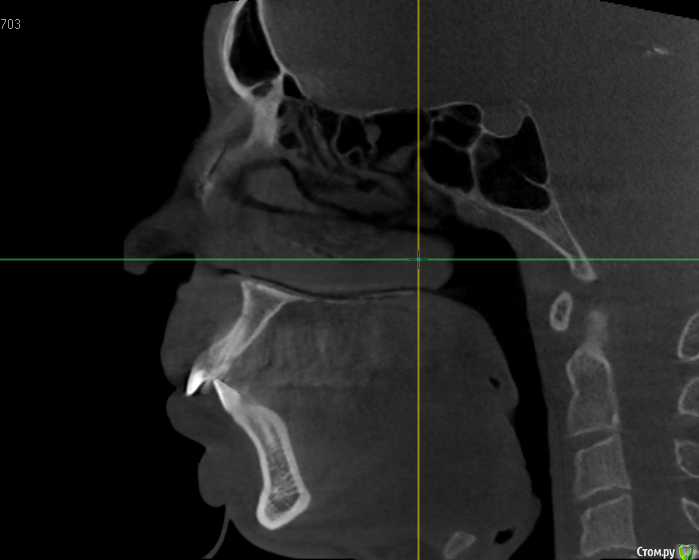

Собираюсь надеть брекеты, на консультации ортодонт сказала, что нужно удалять верхние 4ки и один нижний зуб справа (слева 6ки у меня нет). Действительно ли это необходимо? Просто все чаще натыкаюсь на случаи, когда люди потом обратно раздвигают зубы и ставят импланты. Вот КЛКТ 16x16 - https://yadi.sk/d/40q5jLjb3JUzLN

ТРГ нет, только КТ. Хотелось бы понять, оправдано ли удаление верхних четверок. + ко всему корни их вроде как выступают в пазуху, это тоже лишние осложнения. Был у 3х ортодонтов, один как увидел КТ предположил, что скорее всего нужно будет удалять, другой сказал что ничего не надо, что перетянем все назад и так, третий сказал что пограничный случай, в ходе лечения разберемся (правда смотрел он только панорамный снимок). Мнения очень полярные